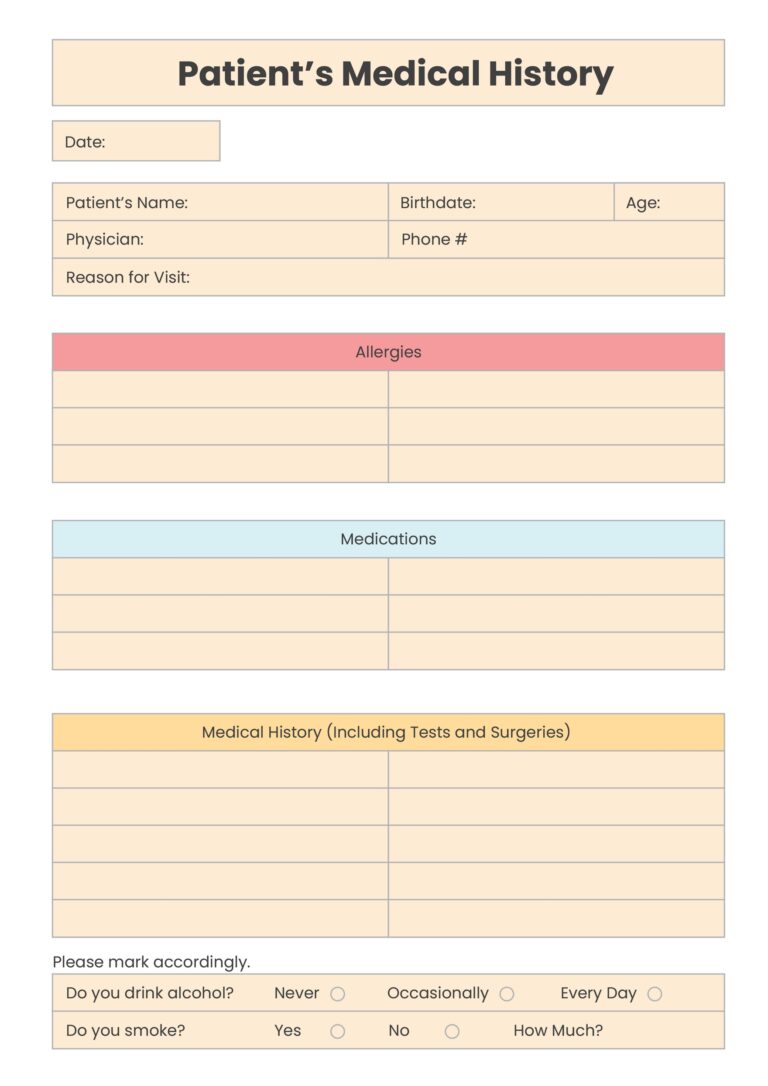

Printable Patient Chart

March 14, 2025

Are you in need of a convenient way to keep track of your medical history and appointments? Look no further...

Read more